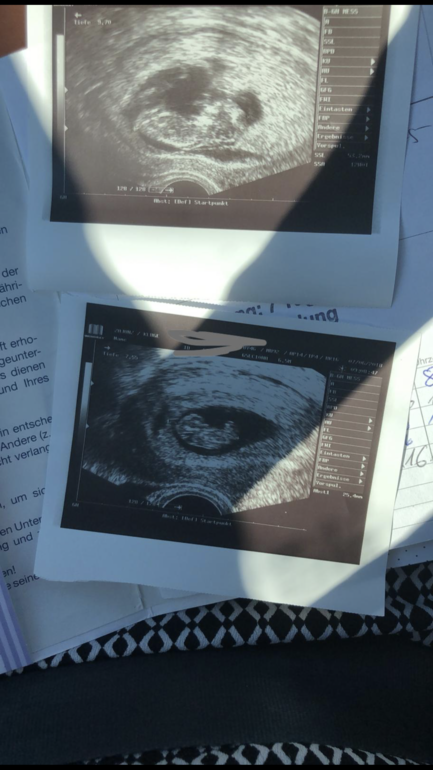

Плодное яйцо деформировано?

Анализы, скринингиВерхнее узи сегодня, нижнее раньше. Врач сказал яйцо деформировано,гематома и закончиться ли Беременность рождением здорового ребёнка неизвестно. Чем это грозит? Кто сталкивался? Можете писать и негативный опыт. Спасибо.срок 11.5 Фото в коментарии

А что про малыша, какие показатели? На сохранение в больницу может??? У меня тоже был гипертонус, яйцо деформировано, на 10 неделе. Пролежала в больнице, уколы папаверина, свечи. Все хорошо сейчас.

У меня из за гипертонуса было дефармировпнно плоднле яйцо (ладьевидной формы) но это было на 8-9 неделе. Пила магний Б6 + паповерин свечи+ на ночь ношпа и дюфастон. К12 неделям (1скринингу ) все нормализировалось ,магний продолжаю пить по сей день.